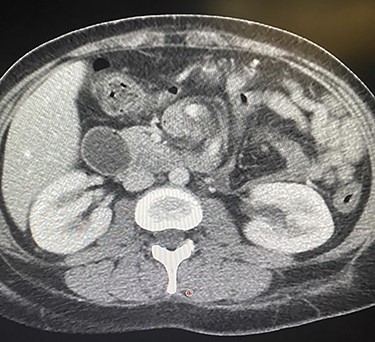

The patient taken to the operating room for diagnostic laparoscopy and proceed, after insufflating the abdomen the whole abdomen examined and showed proximal dilatation of small intestine with collapse of distal part of jejunum, the ileocecal junction identified and the small bowel examined proximally till the obstruction identified, which is fibrous band originating from the stomach to the proximal part of jejunum (Fig. 3), examination of this band showed that this band is caused by suture penetrating the stomach wall, which is going with the previous history of the endoscopic gastroplasty, reduction of the internal hernia done by releasing of the fibrous band, the herniated segment was healthy (Fig. 4).

Fibrous band originating from the stomach to the proximal part of jejunum.